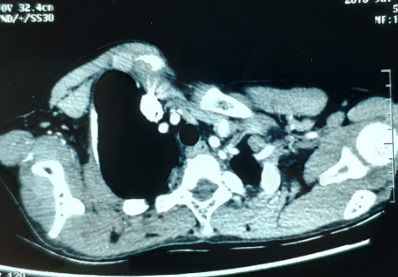

入院查体:右侧颈部有陈旧性手术疤痕,右侧胸锁关节突起,右侧前胸壁突起,伴胸骨附近凹陷。术前CT检查:右侧前胸壁明显突起,左右胸廓不对称。其他检查未发现手术禁忌。

图1,胸锁关节突起,右侧胸壁突起。